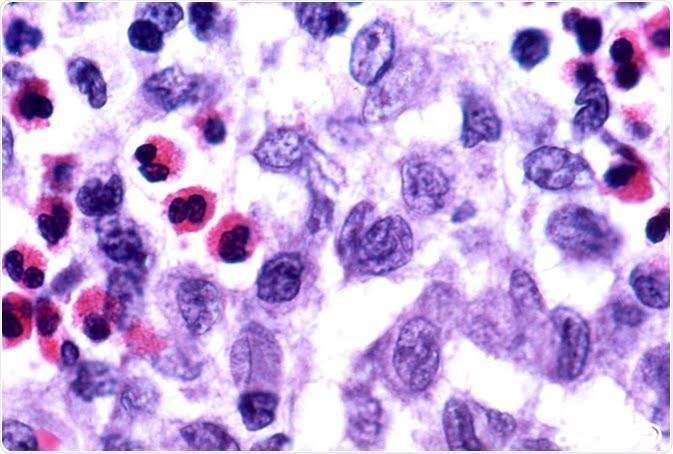

Langerhans cell histiocytosis (LCH) is a rare disease that begins in LCH cells. LCH cells are a type of dendritic cell that normally helps the body fight infection. Sometimes mutations (changes) develop in genes that control how dendritic cells function. These include mutations of the BRAF, MAP2K1, RAS, and ARAF genes.